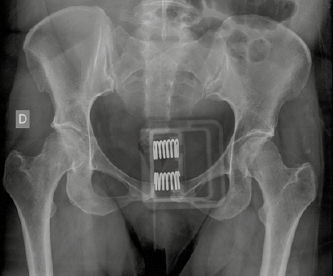

Se solicitó la colaboración de los especialistas del servicio de Traumatología del hospital, quienes de inmediato indicaron la colocación de un cinturón pélvico slip-sling que permitió a la paciente la sedestación y la deambulación de pequeñas distancias y tener menos dolor. Se indicó tromboprofilaxis con bemiparina sódica a la dosis de 3500 UI cada 24 h por vía subcutánea. En la radiografía de control tomada después de la colocación del cinturón se observó una reducción de la diástasis hasta los 18 mm. Figura 2

Figura 2 Reducción de la distancia entre ambas ramas púbicas a 18 mm después de la colocación del cinturón pélvico slip-sling.